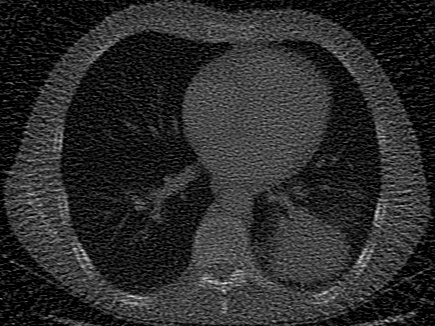

| Computed Tomography (CT) [28] | 2D | X-ray CT scan of a human chest, used to evaluate signal recovery in a classic underdetermined inverse problem. |

In addition to synthetic experiments, we evaluate each model on diverse tasks involving real-world 2D images and 3D volumes. These experiments assess the models’ ability to overfit, generalize, and solve inverse problems with natural signals. We use 10 images from DIV2K [27] to test image overfitting, super-resolution, and denoising at two different levels of Gaussian noise. We use 7 CT scans, including a 2D chest CT scan from Clark et al. [28] and 6 CT scans from the Generalizable Dose Prediction for Heterogeneous Multi-Cohort and Multi-Site Radiotherapy Planning challenge at AAPM 2025 [31], to evaluate performance in a classic underdetermined inverse problem, in which the task is to recover an image from undersampled X-ray projections. We evaluate volumetric performance using the occupancy function and surface of the 3D Stanford Dragon [29]. On both of these 3D signals we test both volume overfitting and super-resolution. Our real-data signals and tasks are summarized in the bottom half of Table˜1, with further details provided in Section˜5.4.

Computed Tomography (CT).

For CT experiments, we train models on a real chest CT slice from the dataset in Clark et al. [28], which was also used in WIRE [16]. The training data was 100 projection measurements of the original 326435 chest CT slice, forming a 100435 sinogram equivalent to approximately 30% of the total pixel count in the original image. Since this inverse problem is inherently underdetermined, we apply TV regularization in our Grid model. The TV hyperparameter was tuned using the classic Shepp-Logan phantom image [37] as a reconstruction target.